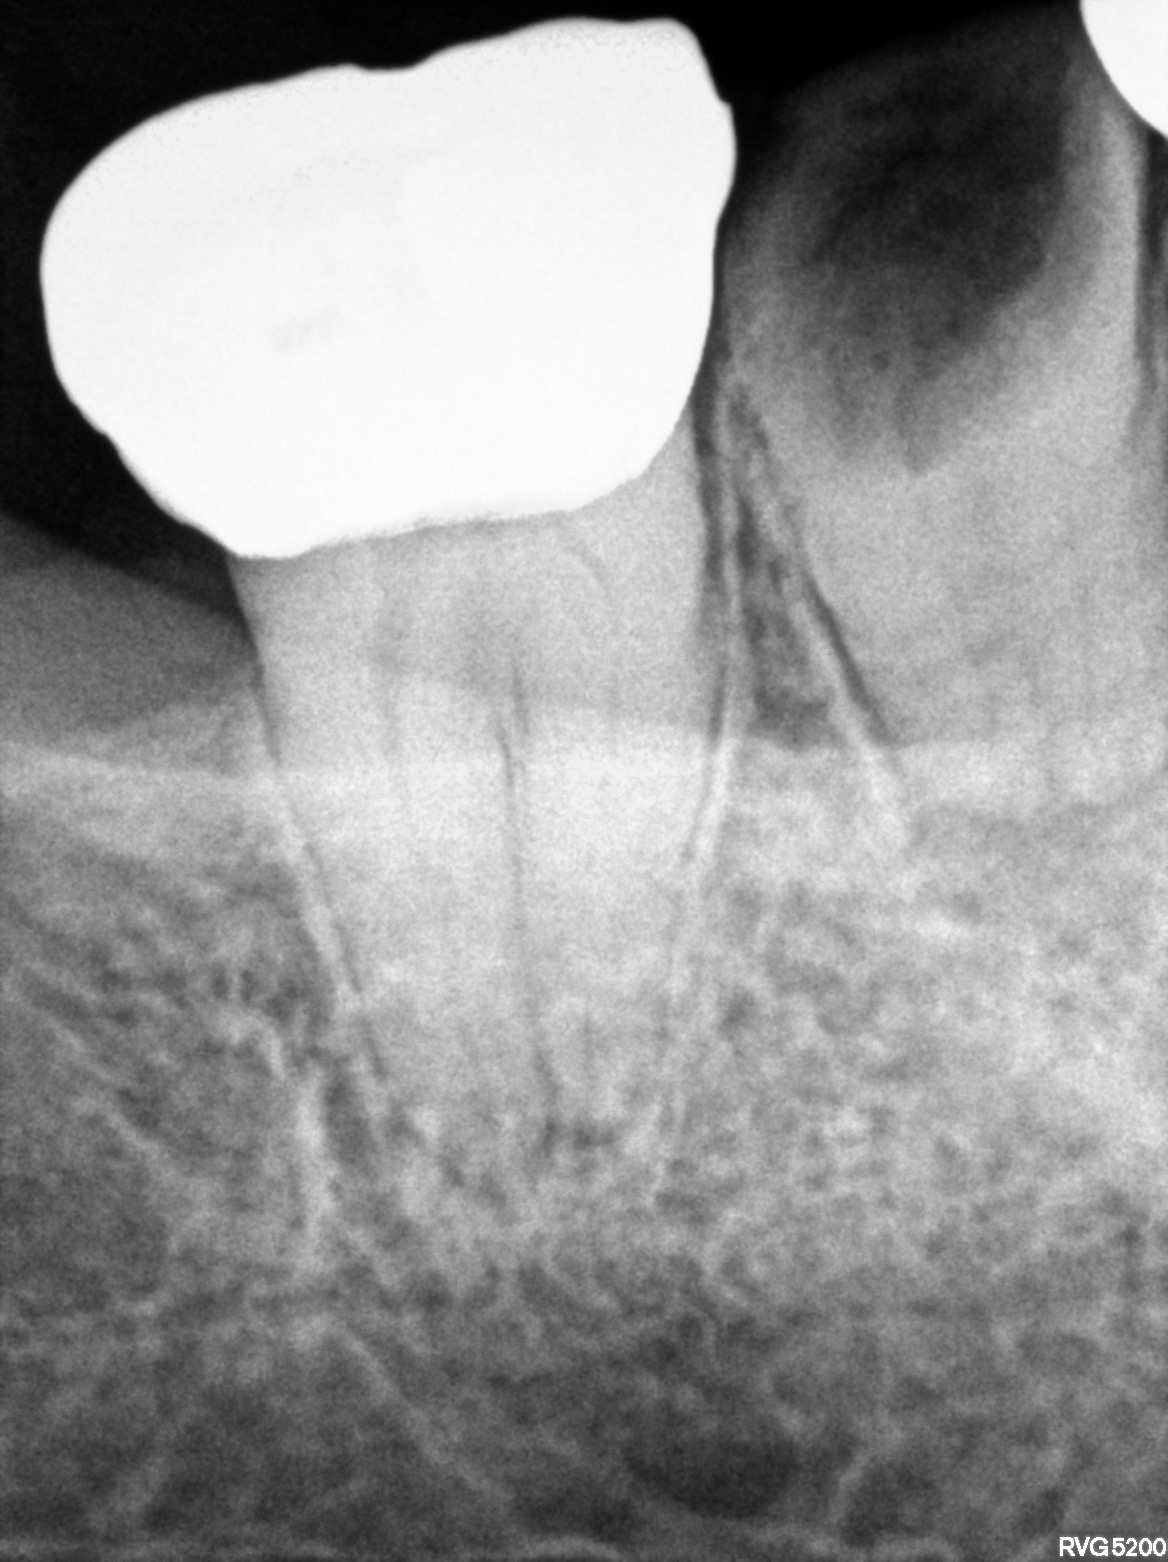

Dental Radiographs FHIR: DocumentReference · LOINC 24641-7

d (14).jpg

24641-7